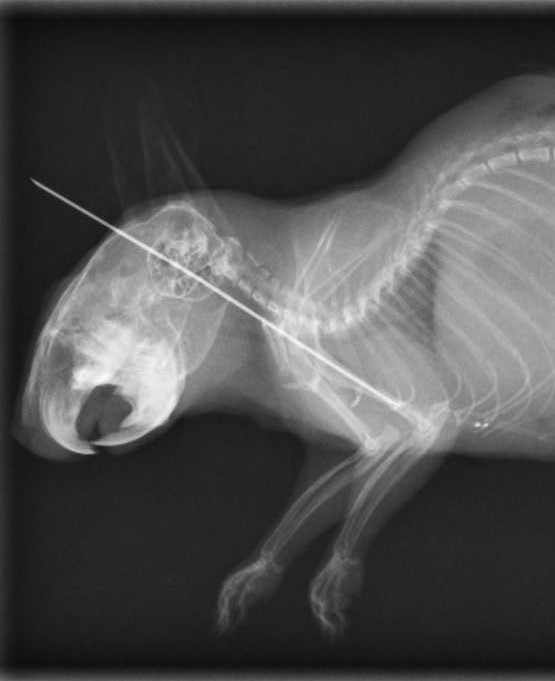

【診断】

骨折すると、足を浮かせて着地を避ける、異常な角度での四肢の保持、動きの低下、痛みを訴えるような行動などが観察されます。視診と触診に加え、レントゲン検査が確定診断に必要です。画像により骨折の位置、ずれの有無、骨片の数や形状、関節への影響などを把握し、治療方針を決定します。